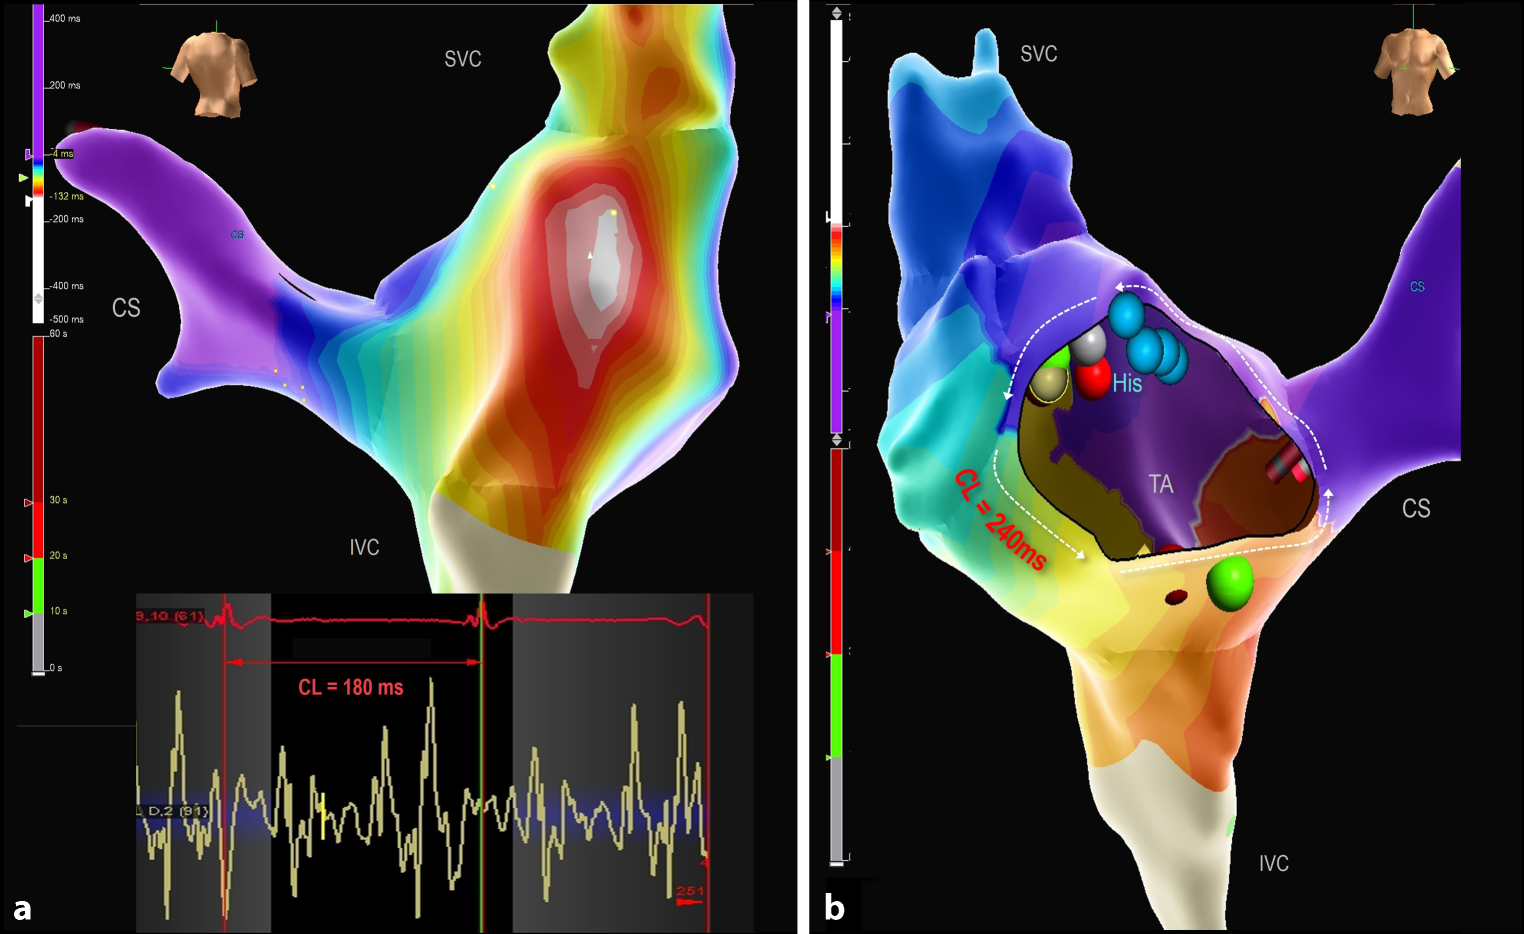

Patient 6 exhibited two types of atrial tachycardias: a very fast focal micro-reentrant tachycardia (CL 180 ms) associated with a fragmented area in the upper part of the right atriotomy scar, and a cavotricuspid isthmus (CTI) dependent counterclockwise atrial flutter (CL 240 ms). The focal RA tachycardia was addressed first, and followed by CTI ablation, resulting in bidirectional CTI block (Fig. 3).

Fig. 3

3D local activation maps of the right atrium showing two different SVT mechanisms in an infant with mitral valve stenosis and multiple ventricular septal defects. a Modified postero-anterior view shows a micro-reentrant tachycardia with a cycle length (CL) of 180 ms related to a very fragmented area in the upper part of the atriotomy scar as depicted by the intracardiac signals recorded by the mapping/ablation catheter. b Anteroposterior (right side) view showing a cavotricuspid isthmus (CTI) dependent counterclockwise atrial flutter with a CL of 240 ms. CTI was blocked with 3 RF applications (one green dot and one red dot partly visible at CTI position). Blue dots demarcate His position; the green, red, and grey dots next to the blue His dots, mark the location of the micro re-entrant tachycardia on the posterior wall. CS coronary sinus, IVC inferior vena cava, SVC superior vena cava, TA tricuspid annulus